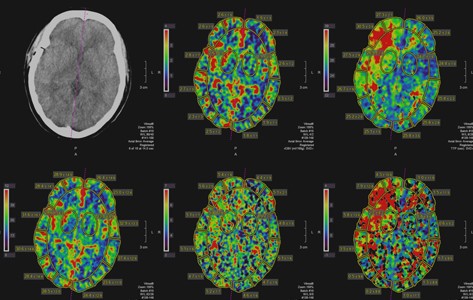

Neuroradiology

Neuroradiology is the subspecialty of radiology that conducts imaging of the brain including the neck, head and spine. Imaging techniques for the brain, spine and neck can include X-ray, CT, MRI and ultrasound.

Our neuroradiologists diagnose many medical conditions, including:

- Stroke

- Aneurysm

- Central nervous system tumors

- Neurological disorders

- Congenital anomalies

- Staging for Alzheimer’s disease

- Staging for multiple sclerosis

- Staging for cancer

- Early state neurological dysfunction